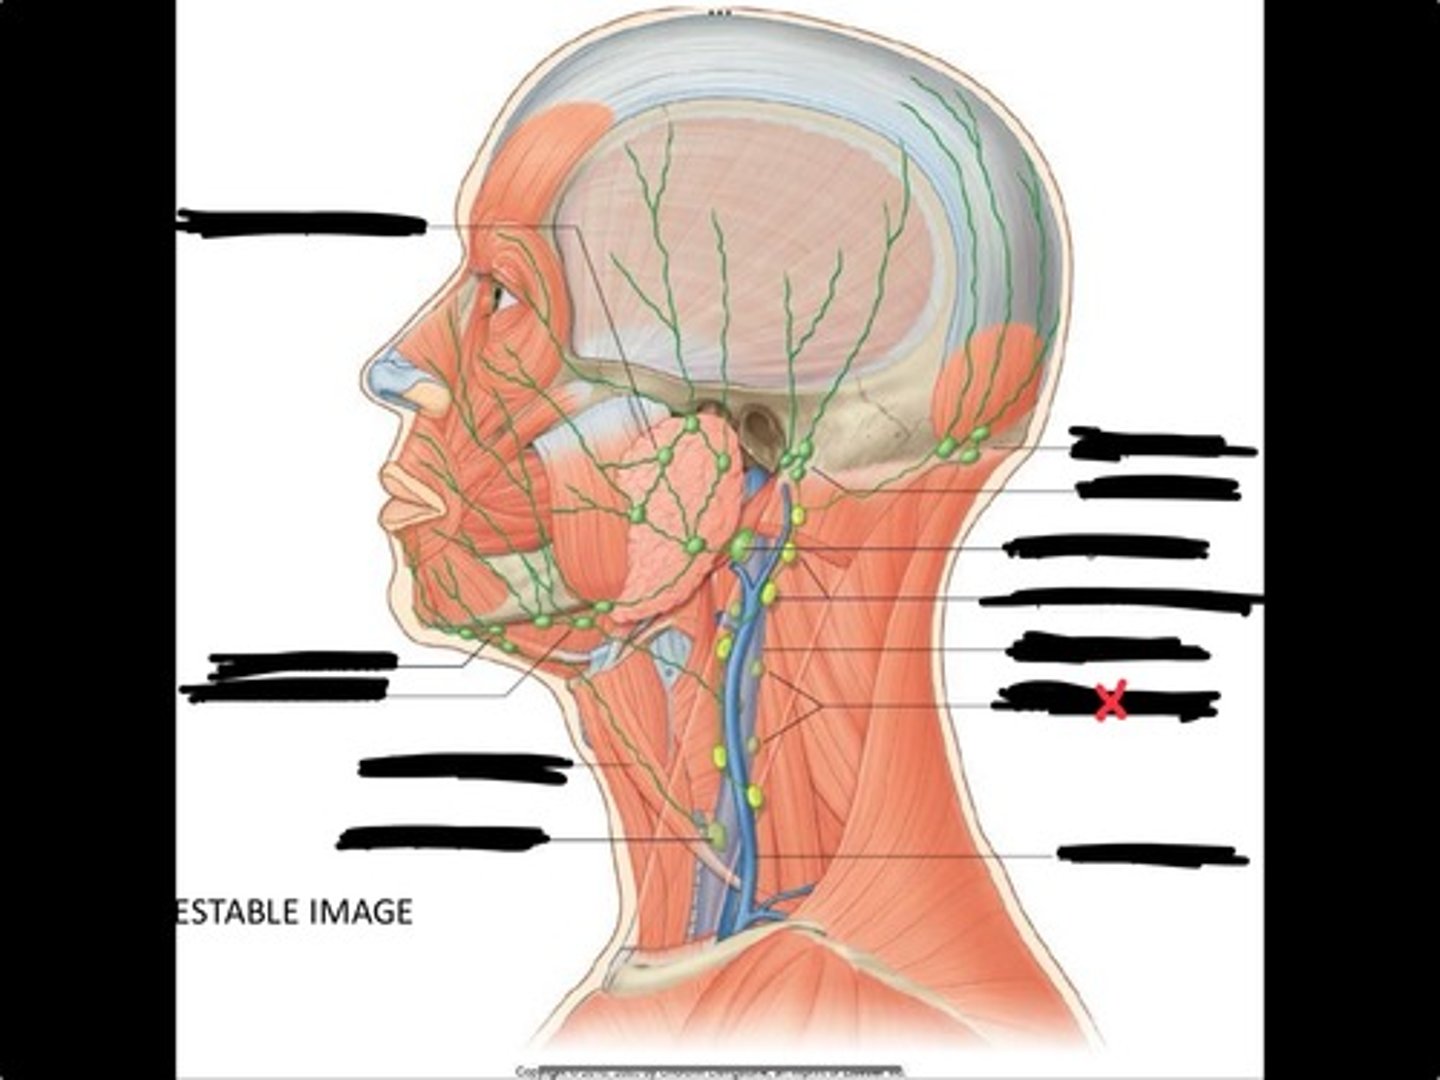

Jugulo-omohyoid node

Omohyoid muscle

Submandibular nodes

Submental nodes

Pre-articular/parotid nodes

Occipital nodes

Mastoid nodes

Jugulodigastric nodes

Superficial cervical nodes

Internal jugular vein

Deep cervical nodes

External jugular vein